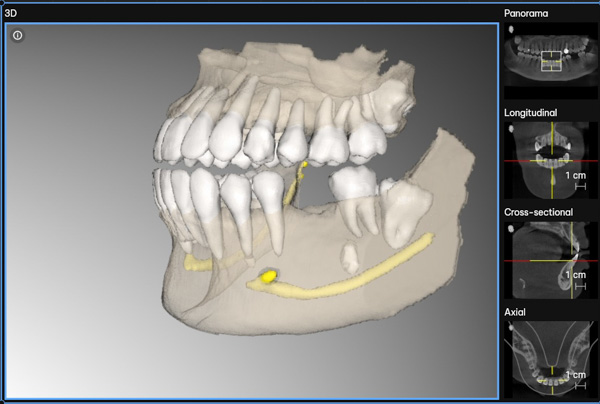

1. Comprehensive Implant Assessment

Your implant journey begins with a thorough assessment to determine the bone levels, bone width, and overall suitability for dental implants. This step ensures we select the best treatment plan for your specific needs. We offer two types of implant procedures: